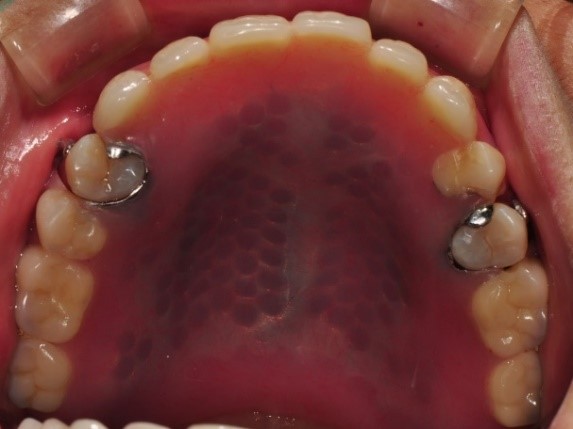

治療後-下顎

裝上活動式假牙-下顎